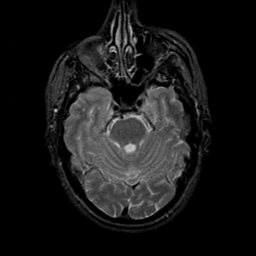

MR Study #23, January 26, 1992 -- Slice #15